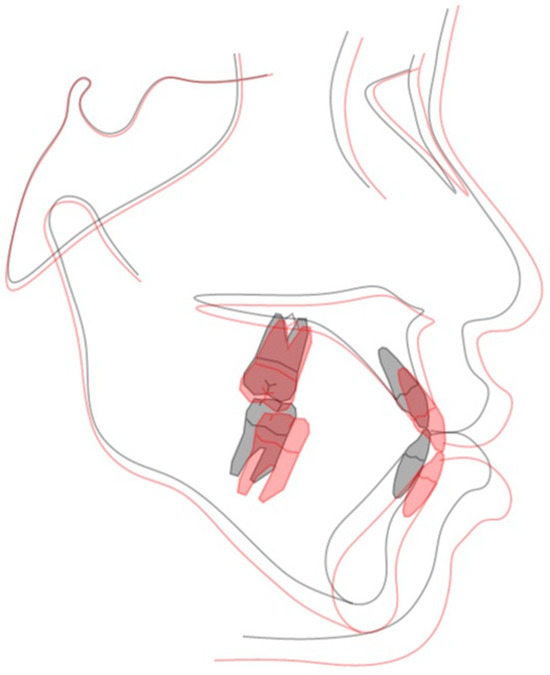

2.4. Treatment Progress

2.5. Treatment Results